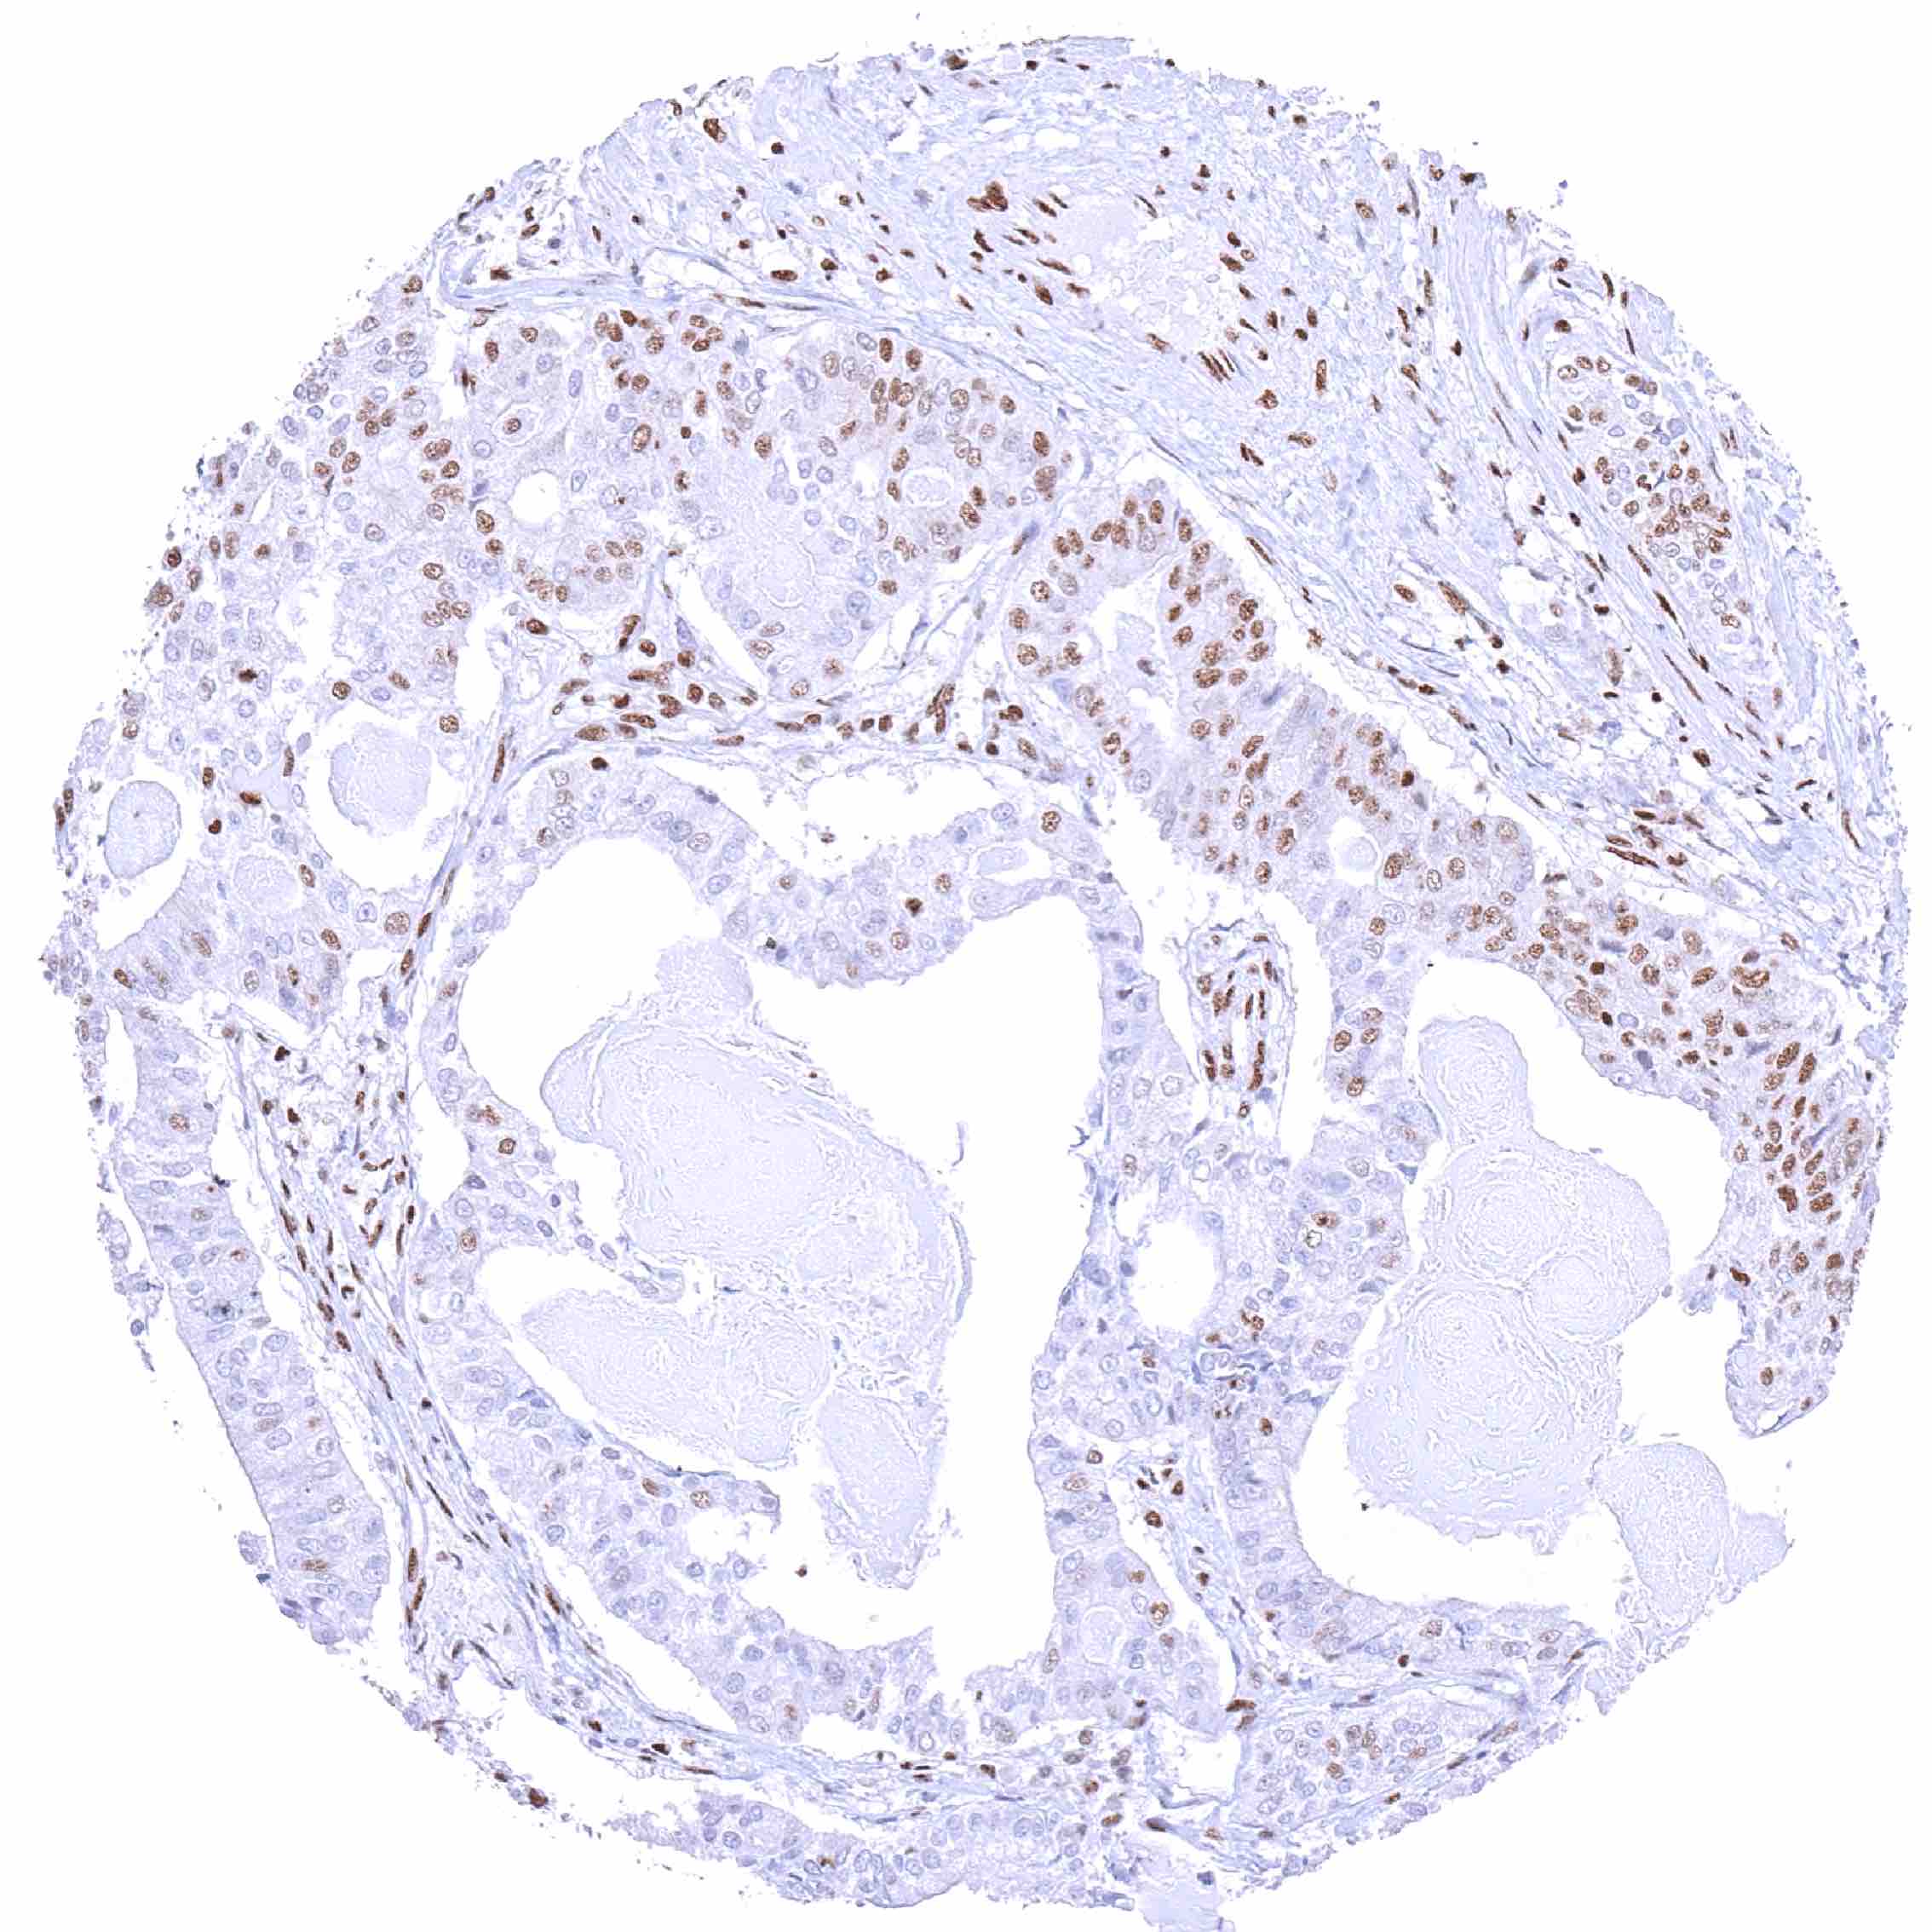

Prostate – Adenocarcinoma (Gleason 3+3=6) with only a weak BRD4 staining of tumor cells while staining is markedly more intense in non-neoplastic glands.